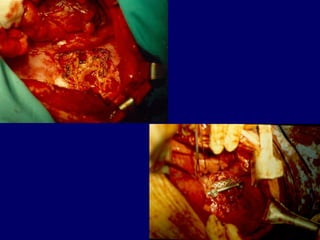

Anterior

PUS evacuation

Bilaterally

Laminectomies

Post posterior PUS

evacuation